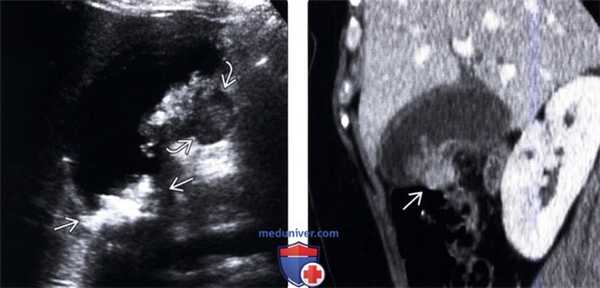

(Левый) У женщины 37 лет с острыми болями в правом верхнем квадранте живота на сагиттальном УЗ срезе желчного пузыря визуализируются отбрасывающие тень конкременты и сладж, а также опухолевидное дольчатое локальное утолщение стенки, прорастающее трансмурально.

(Правый) При КТ с контрастным усилением в режиме мульти планарной реконструкции в той же сагиттальной плоскости определяется полипоидное объемное образование стенки желчного пузыря, накапливающее контраст.

(Левый) При динамической МРТ в постгадолиниевую фазу в корональной плоскости наблюдается отсроченное прогрессирующее накопление контраста дольчатым полипоидным образованием, также виден дефект контрастной стенки желчного пузыря.

(Правый) У этого же пациента при МР холангиопанкреатографии определяются конкременты шейки и тела желчного пузыря и дольчатое полипоидное образование, пролабирующее в просвет желчного пузыря.